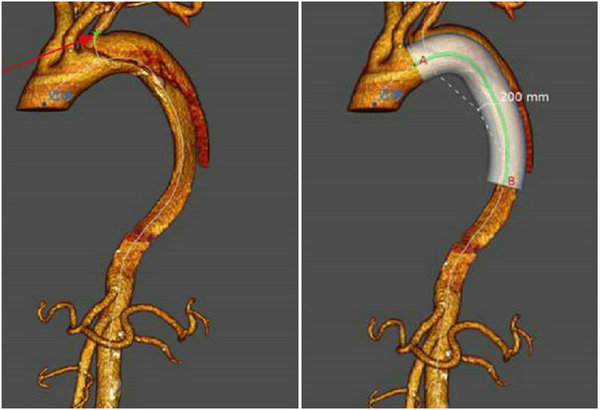

术前CTA,夹层破口位于左侧锁骨下动脉开口处后方